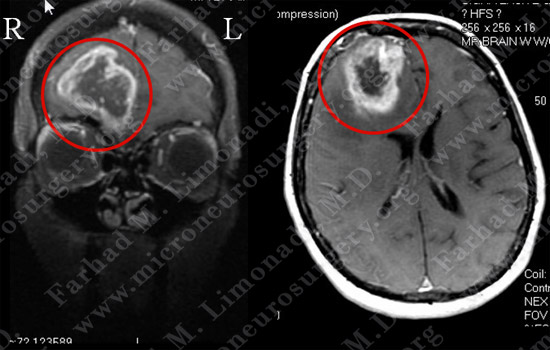

Imaging

MRI scan of the patient’s brain shows a large right frontal ring-enhancing tumor.